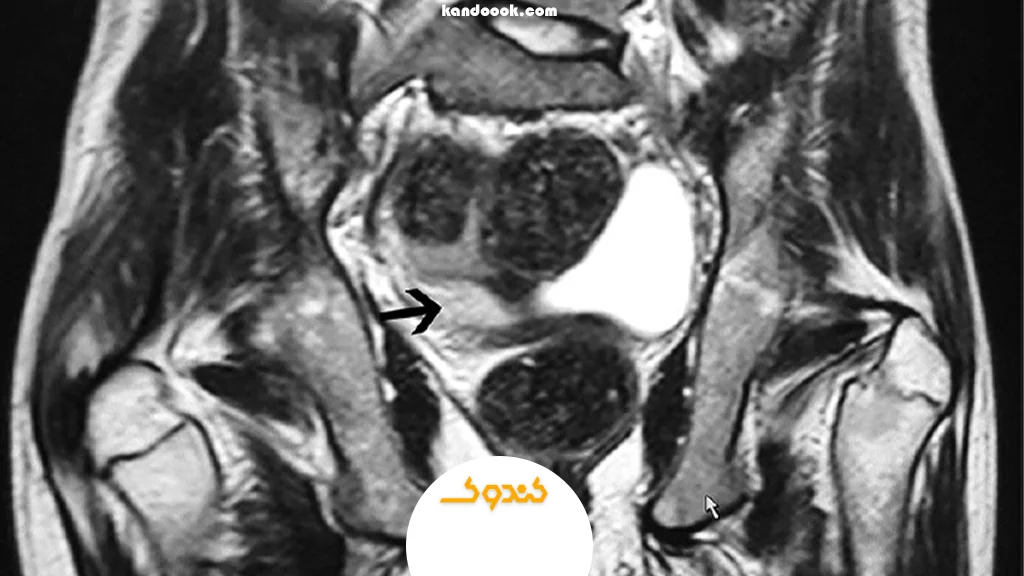

MRI رحم و لگن

برای موارد پیچیده، فیبرومهای بسیار بزرگ، تودههای دیوارهای یا زمانی که نیاز به بررسی دقیق بیشتر باشد، MRI بهترین گزینه است. این روش جزئیات بسیار بیشتری از بافتها نشان میدهد و میتواند فیبرومها را بر اساس نوع و محل تفکیک کند.